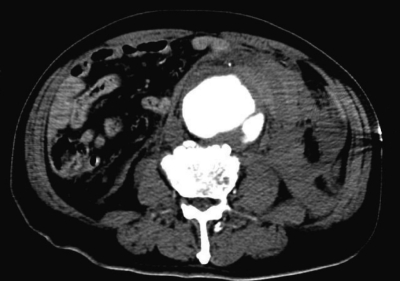

血液所見:赤血球 315 万、Hb 10.0 g/dL、Ht 30 %、白血球 13,800、血小板 15 万。血液生化学所見:総蛋白 4.8 g/dL、アルブミン 3.3 g/dL、総ビリルビン 1.8 mg/dL、直接ビリルビン 0.2 mg/dL、 AST 92 U/L、 ALT 54 U/L、 LD 379 U/L (基準 176〜353)、ALP 129 U/L (基準 115〜359)、γ-GTP 17 U/L(基準 8〜50)、CK 138 U/L (基準 30〜140)、尿素窒素 18 mg/dL、クレアチニン 1.1 mg/dL、血糖 122 mg/dL、Na 135 mEq/L、K5.0 mEq/L、Cl 104 mEq/L。CRP 0.7 mg/dL。動脈血ガス分析(マスク 10 L/分 酸素投与下):pH 7.45、PaCO2 34 Torr、PaO2 166 Torr、HCO3- 23 mEq/L。腹部造影 CTを別に示す。

治療として適切なのはどれか。2つ選べ。

c. 人工血管置換術

e. ステントグラフト内挿術